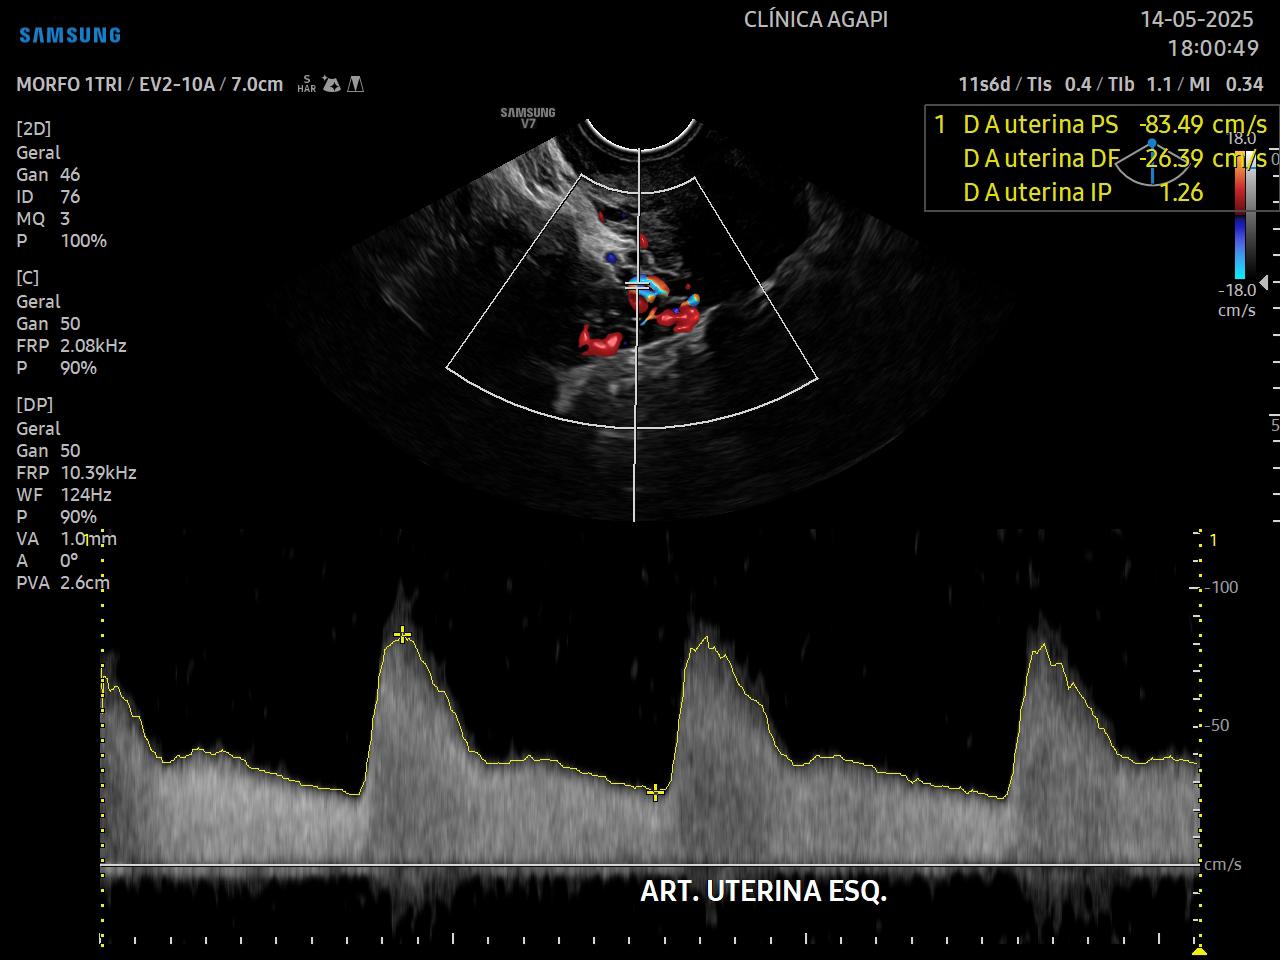

A rastreio de pré eclâmpsia é feito a partir da junção da história materna, pressão arterial média e doppler das artérias uterinas.